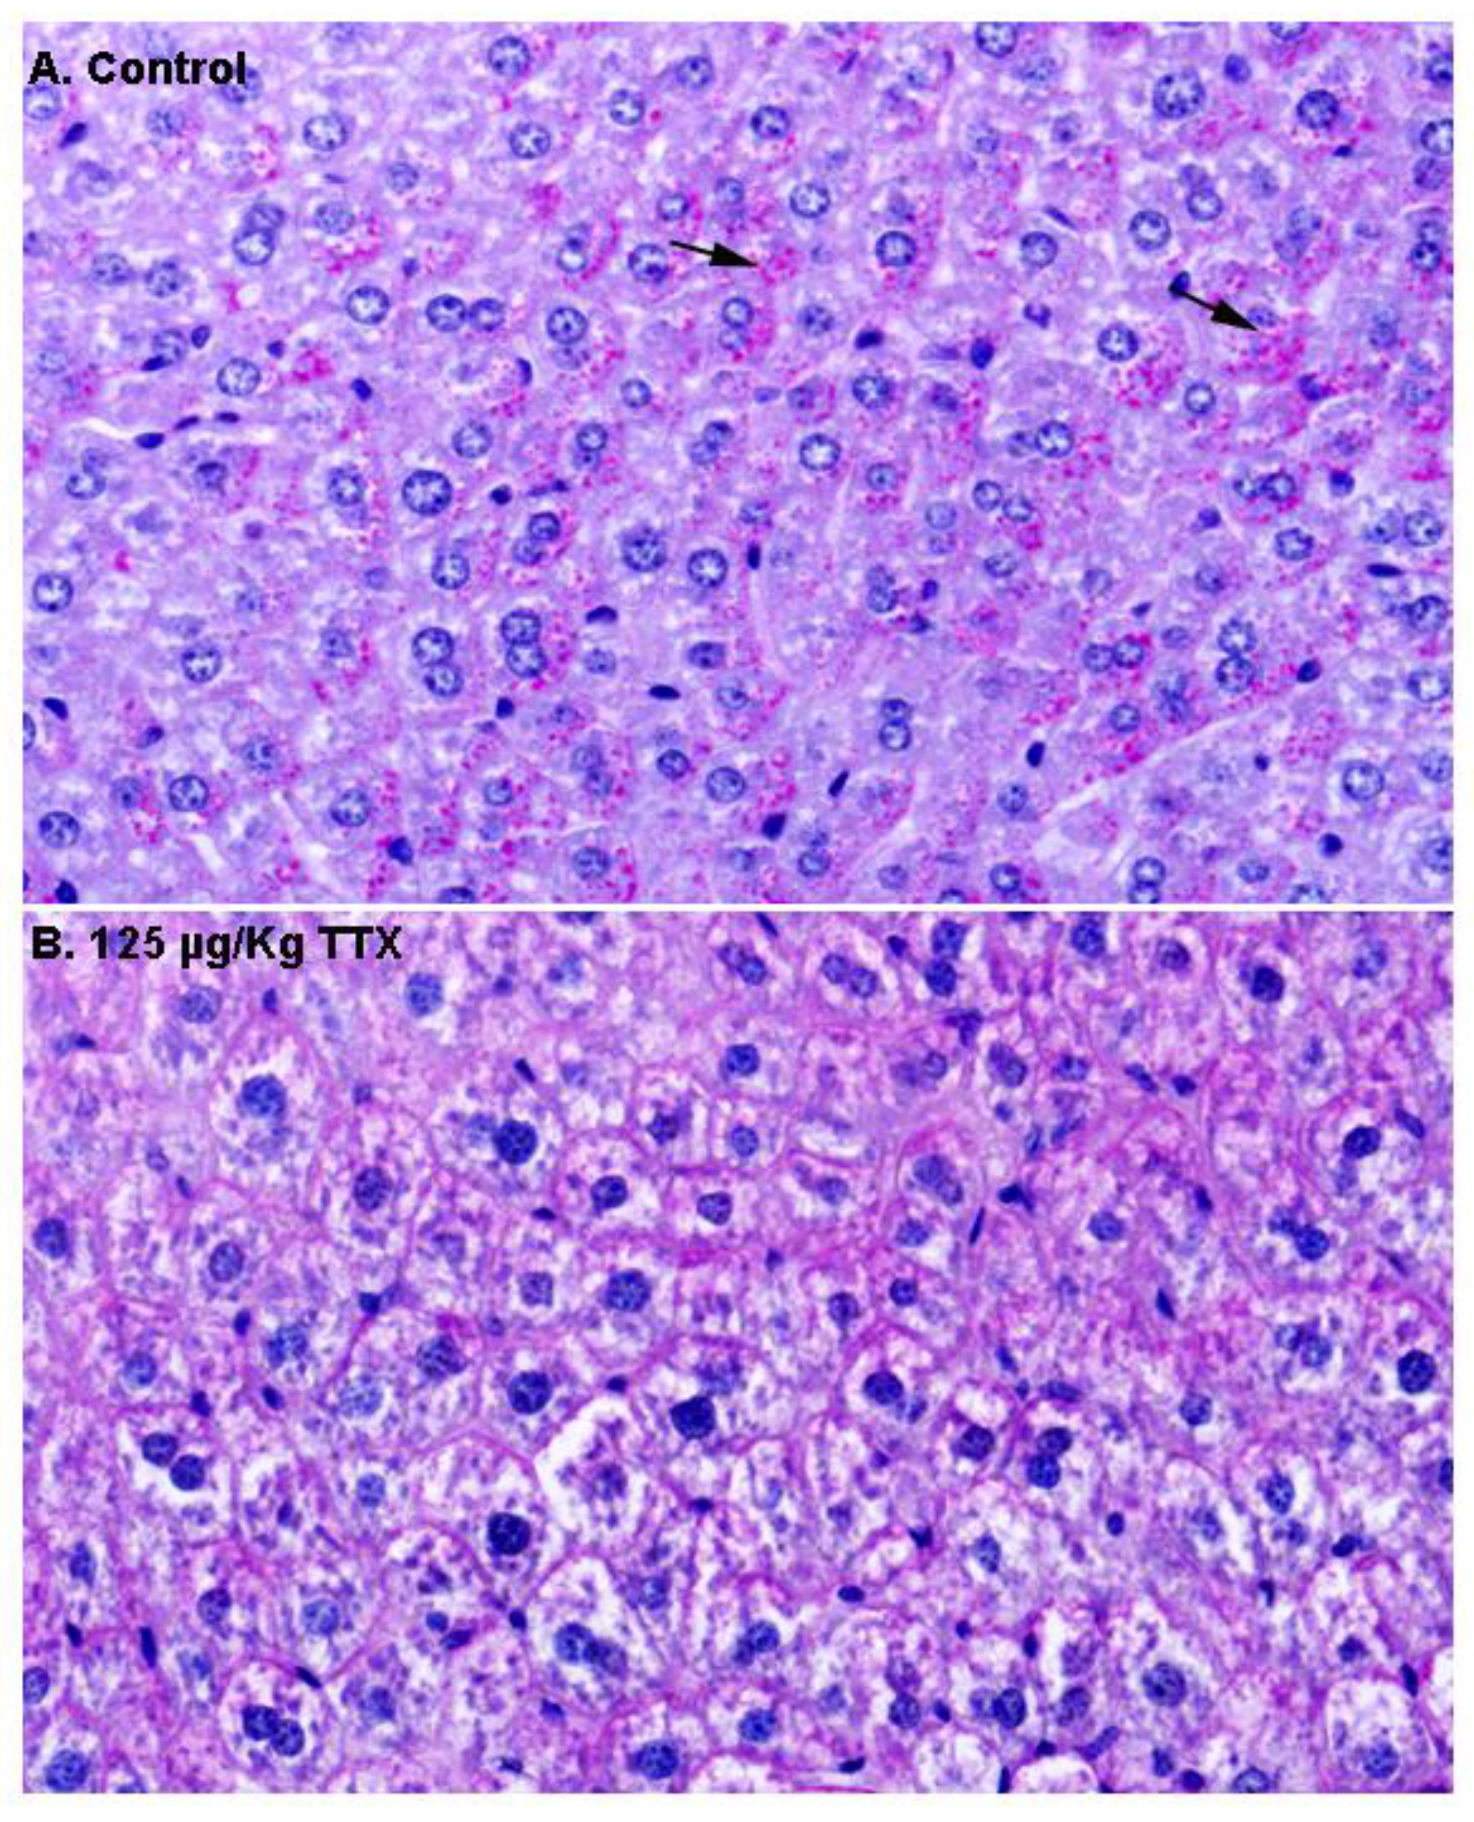

Next, in order to gain more insight into the content of these vacuoles, additional liver sections from control and TTX-treated mice were stained with PAS (Figure 3). As shown in Figure 3A, hepatocytes from control mice were strongly stained with PAS, and magenta granules (indicated by the arrows) considered to represent cytosolic glycogen were observed, while these granules were less evident in hepatocytes from TTX-treated mice (Figure 3B).

Figure 3.

Periodic acid–Schiff (PAS) stained liver sections from control mice and mice treated with TTX at 125 µg/kg (600× magnification). Hepatocytes from control animals were PAS positive, with glycogen (magenta granules indicated by the arrows) located in the cytoplasm (A), while these granules were not present in the hepatocytes from mice dosed daily with 125 µg/kg TTX (B).